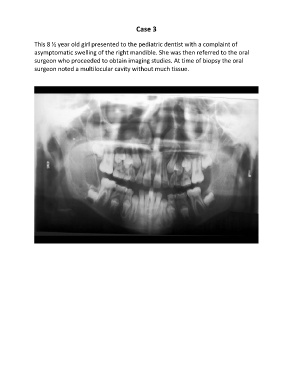

This 8 ½ year old girl presented to the pediatric dentist with a complaint of

asymptomatic swelling of the right mandible. She was then referred to the oral

surgeon who proceeded to obtain imaging studies. At time of biopsy the oral

surgeon noted a multilocular cavity without much tissue.